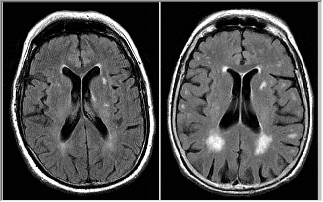

Color to Gray Scale

If the intensity of a color image is the only interested, it is useful to convert the color image to gray scale to reduce calculate complex. Moreover, some input/output devices like monochrome printers or monochrome display, can only handle gray-scale images. In this case, converting color to gray scale is necessary.

Convert a Color Image into Gray Scale,

| Original Image | Gray Scale Image |